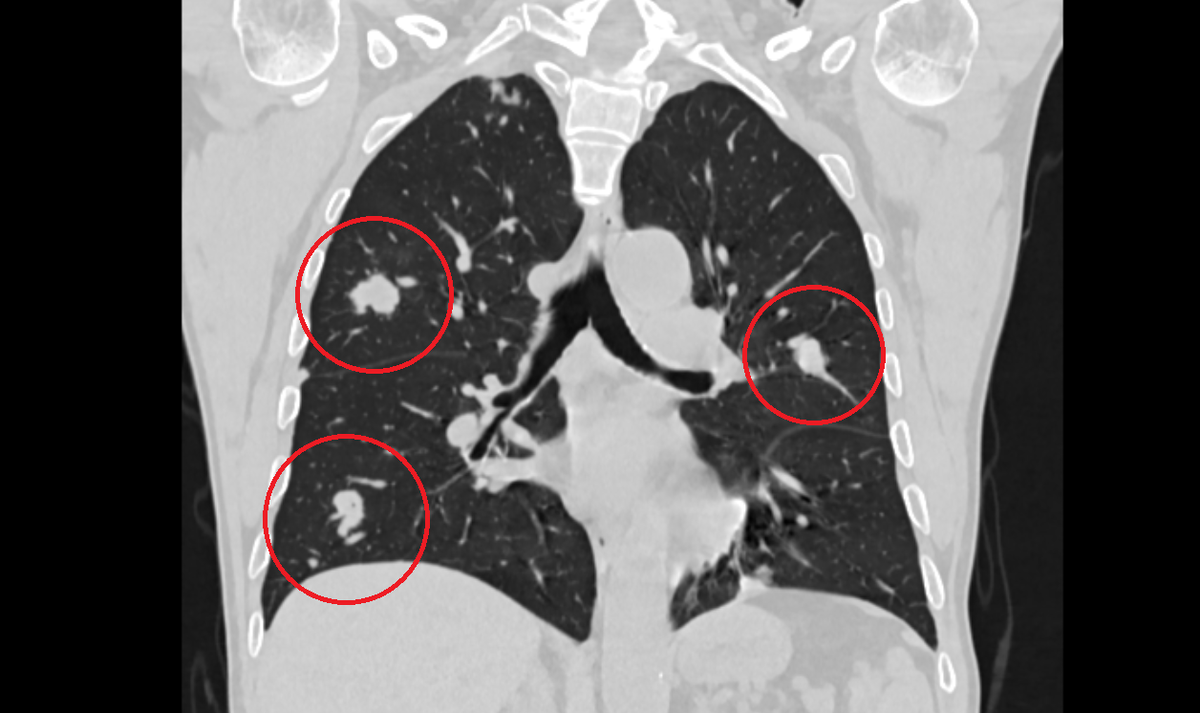

Множественное метастатическое поражение легких. Компьютерная томография.